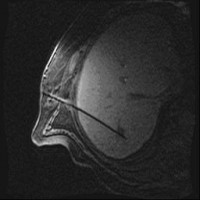

Images: Brachytherapy for liver metastases: first MRI-guided placement of one catheter per tumor followed by irradiation through the catheters using Iridium 192 radiation source.